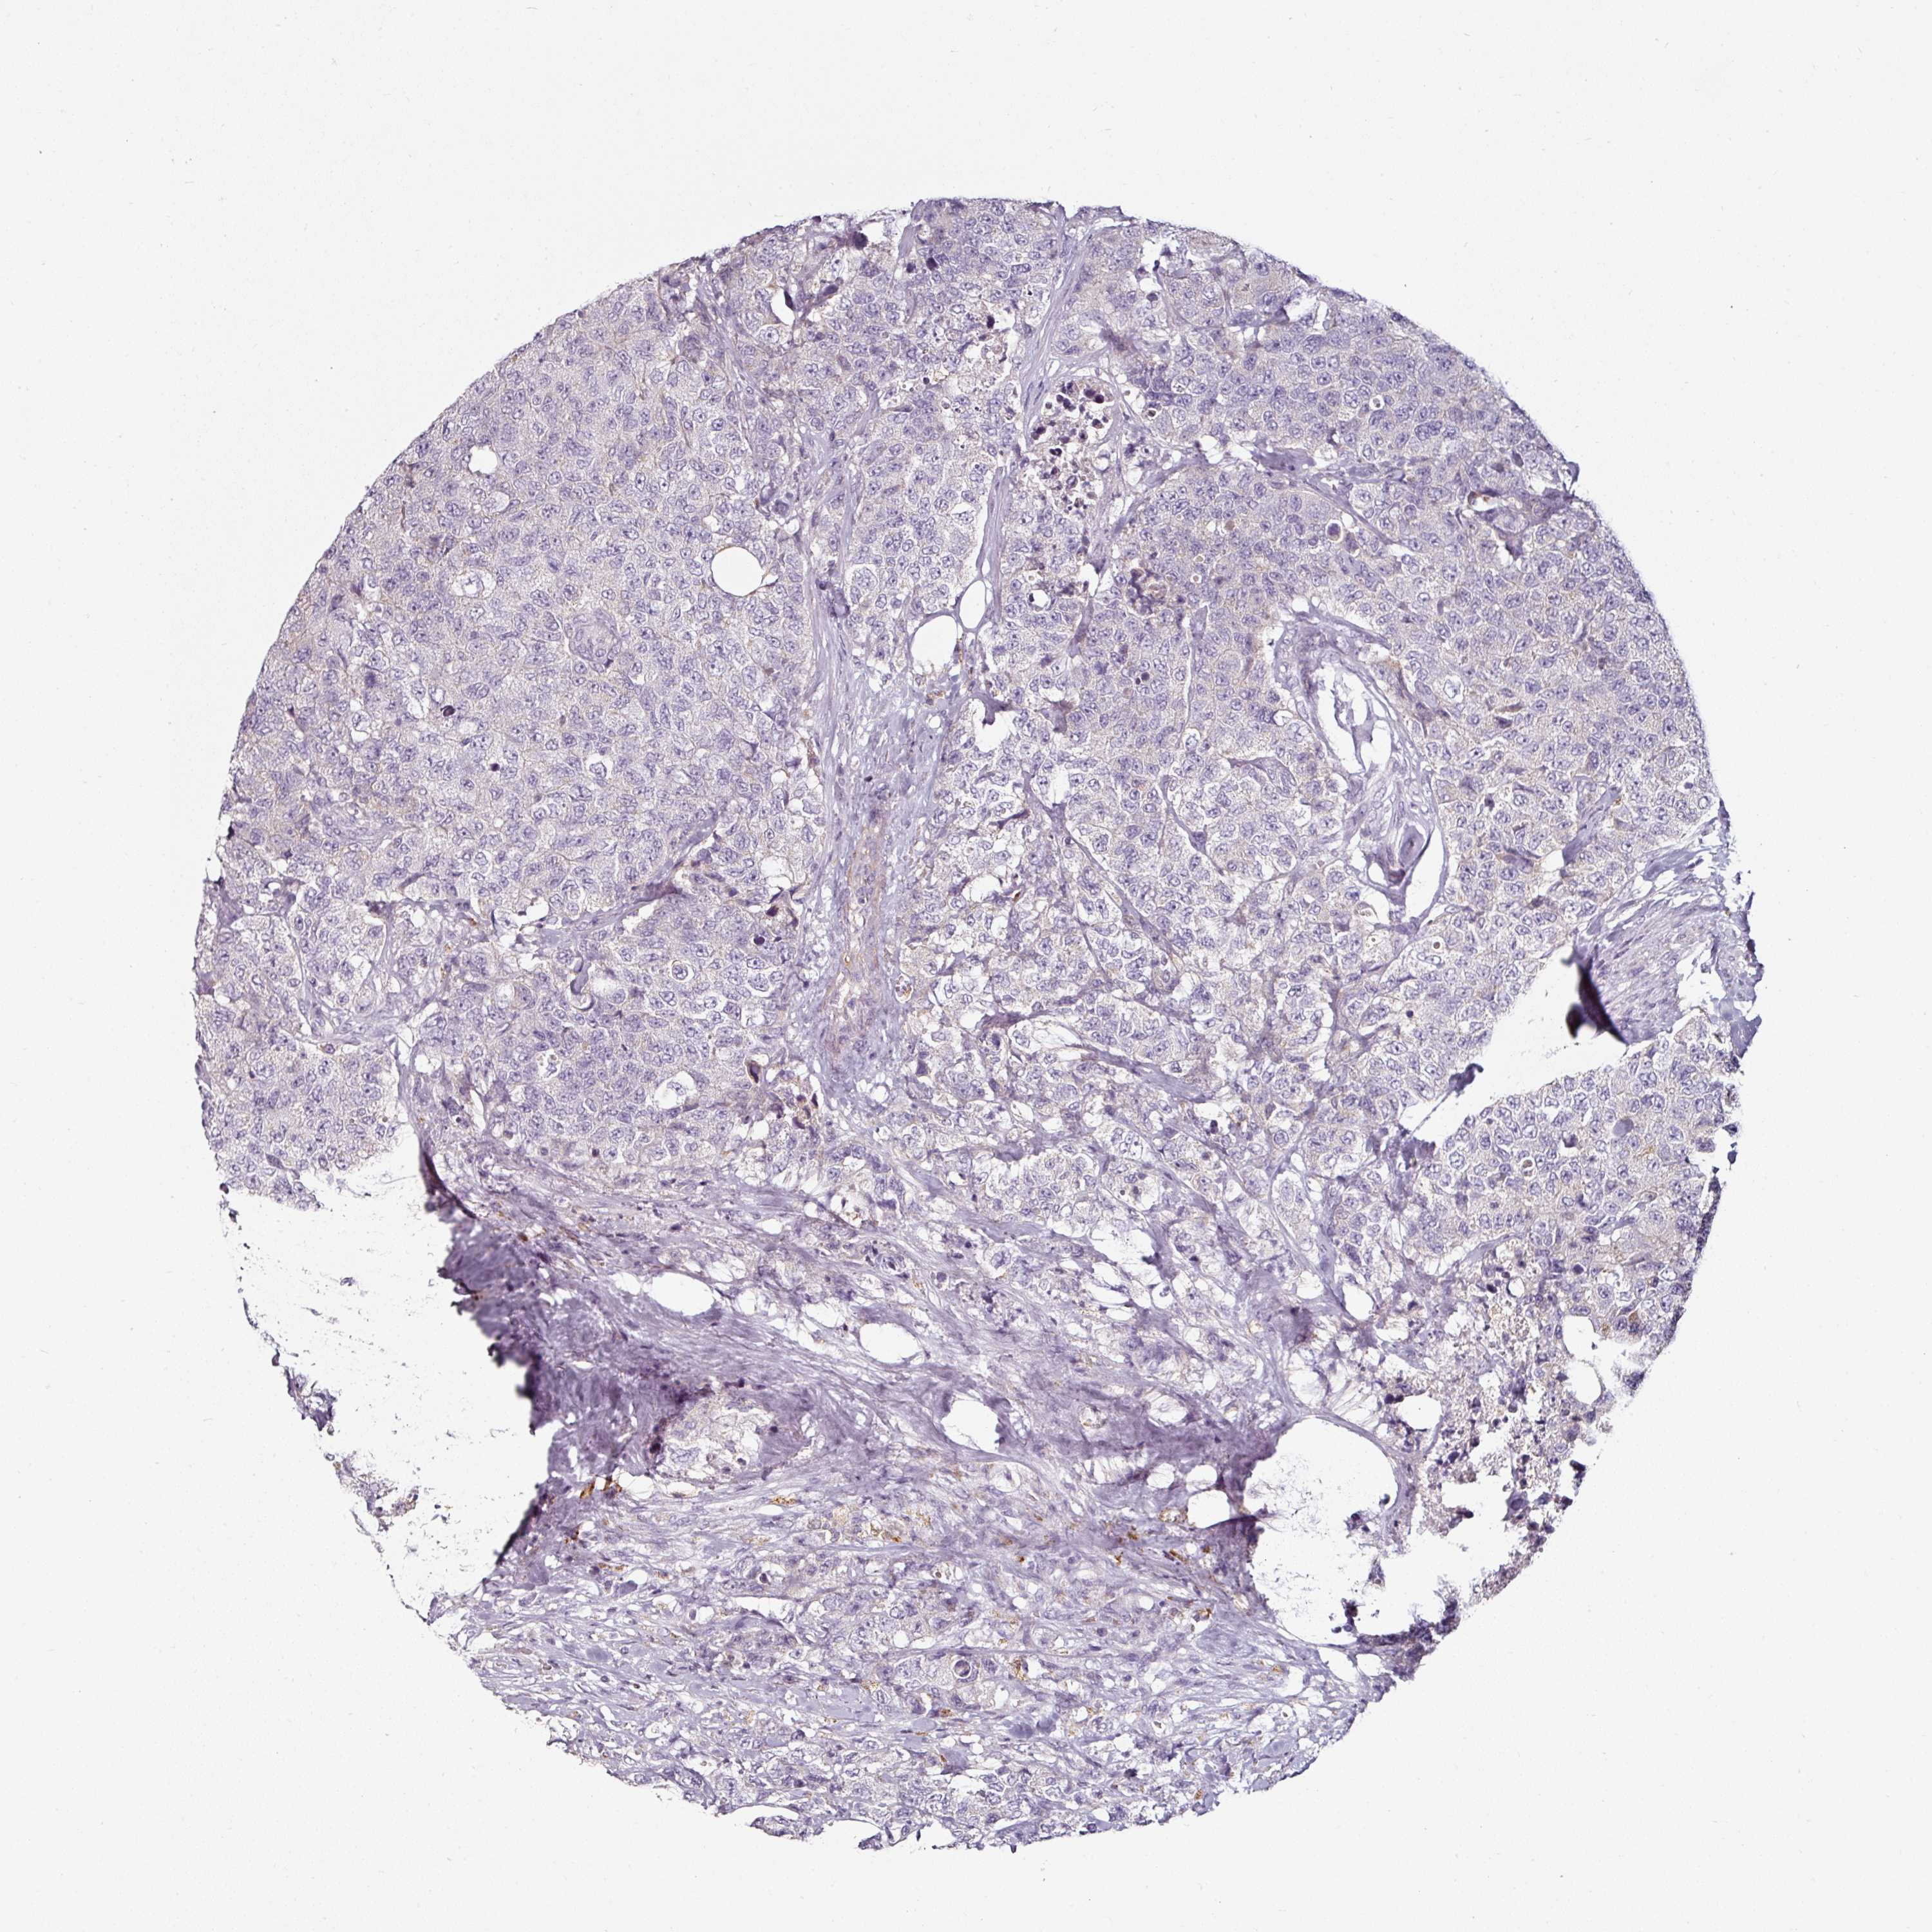

UROTHELIAL CANCER - Protein expressioni

A mouse-over function shows sample information and annotation data. Click on an image to view it in a full screen mode. Samples can be filtered based on level of antibody staining by selecting one or several of the following categories: high, medium, low and not detected. The assay and annotation is described here.

Note that samples used for immunohistochemistry by the Human Protein Atlas do not correspond to samples in the TCGA dataset.

Antibody stainingi

Antibody staining in the annotated cell types in the current human tissue is reported as not detected, low, medium, or high, based on conventional immunohistochemistry profiling in selected tissues. This score is based on the combination of the staining intensity and fraction of stained cells.

Each image is clickable and will lead to virtual microscopy that enables deeper exploration of all samples and also displays staining intensity scores, fraction scores and subcellular localization as well as patient and tissue information for each sample.

Antibody HPA050530

Antibody HPA054147

Staining

High

Medium

Low

Not detected

Intensity

Strong

Moderate

Weak

Negative

Quantity

>75%

75%-25%

<25%

None

Location

Nuclear

Cytoplasmic/membranous

Cytoplasmic/membranous,nuclear

Urothelial carcinoma, High grade

Urothelial carcinoma, NOS

Urothelial carcinoma, Low grade